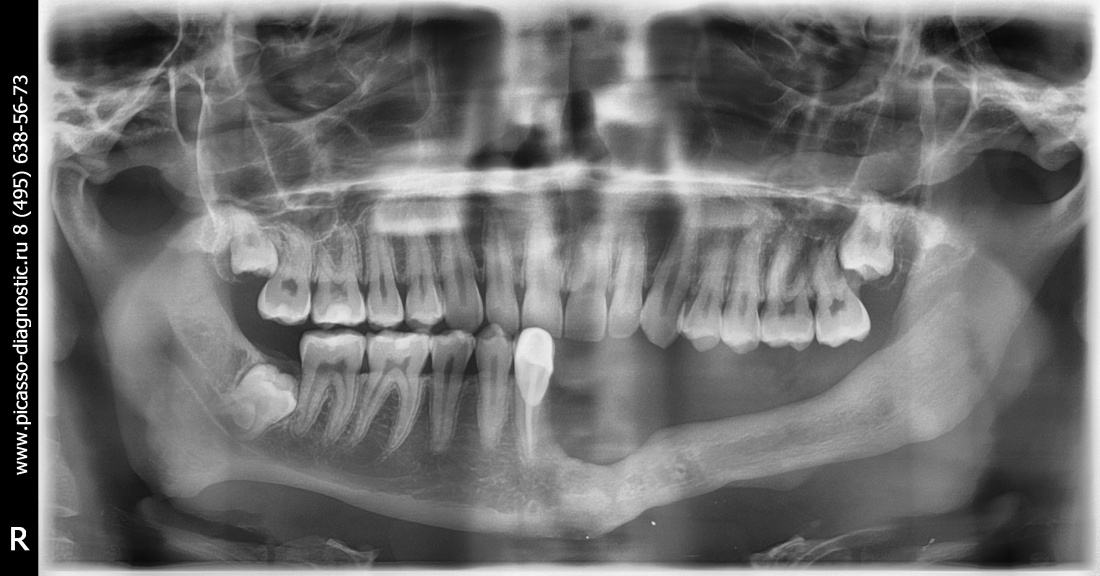

Итак, Елена приехала к нам из Уфы. Клиническая картина на момент обращения:

Собственно, на снимке видно всё, что нам нужно знать. Чуть раньше, чем за полгода до обращения к нам, Елена обратилась в известную уфимскую клинику, где попытались нарастить костную ткань в боковом сегменте нижней челюсти слева, но результат операции оказался неудовлетворительным — на снимке выше заметны остатки использованного ксенографта. После этого ей заявили, что остеопластика в её случае невозможна — и это было заявлено, опять же, известным уфимским специалистом по имплантации. Елене начали склонять к «безальтернативному» варианту — удалению всех зубов, установке четырёх имплантатов во фронтальном отделе с последующим несъемным протезированием. В общем, ей настойчиво предложили лечение по схеме «всё-на-четырёх» или, что модно — All-On-4.